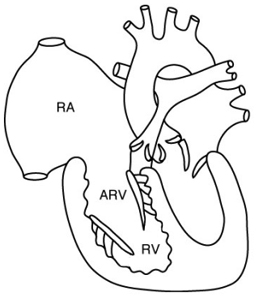

– Insuffisance tricuspide : intérêt de l’IRM dans la maladie d’Ebstein mais pas de quantification aisée de la PAP systolique comme en écho-doppler.

– Insuffisance pulmonaire : quantification de la fraction de régurgitation pulmonaire fiable (anciens Fallots…)